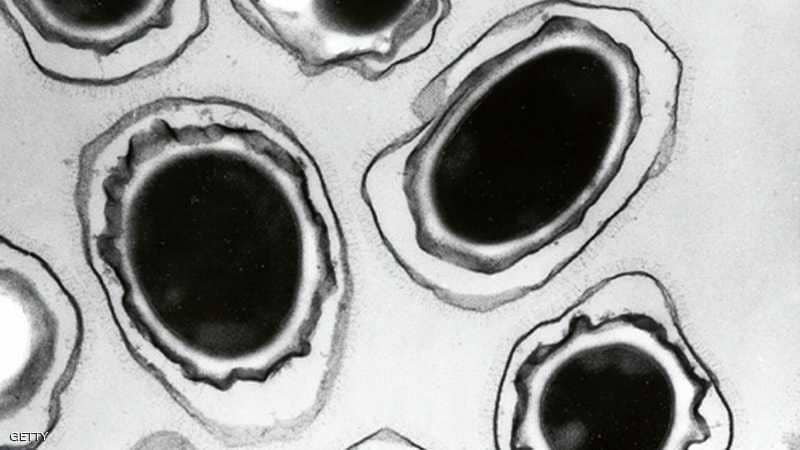

قال مسؤولون في مجال الصحة إنه لا يوجد مؤشر على تباطؤ انتشار البكتيريا الخارقة، أي المقاومة للمضادات الحيوية، في أوروبا، مما قد يزيد صعوبة علاج التسمم الغذائي وغيره من أشكال العدوى.